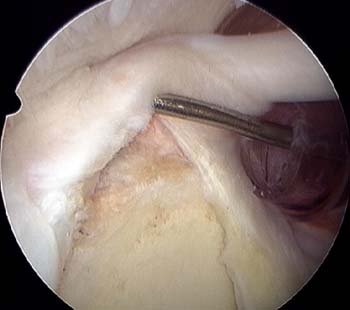

La reparación artroscópica de la lesión SLAP la realizamos en posición de silla de playa con el brazo en tracción manual por un asistente, con 30-40 de Abducción y 20 grados de flexión anterior. Con bloqueo anestésico interescalenico del plexo braquial, más sedación con infusión de propofol y con bomba de infusión continua a 30-35 mmHg. Por un portal posterior estándar para visualización, se realiza una evaluación de la unidad funcional bíceps labrum con un gancho palpador en busca de inestabilidad de la inserción del labrum superior, signo de despegamiento o peel-back, signo de drive through o paso a través. Una vez que se realiza el diagnóstico de lesión SLAP y se decide realizar la reconstrucción artroscópica, se realizan los portales accesorios antero inferior justo por encima del borde superior del subescapular y portal antero supero lateral justo por encima del tendón del bíceps, entrando a nivel del borde antero lateral del acromion. Ambos portales se realizan de afuera adentro, la localización correcta se busca mediante una aguja espinal y se realiza la colocación de cánulas de 7,25 mm con sistema de guías de dilatación progresiva (Arthrex inc. Naples Florida). La cánula antero inferior se la utiliza para manejo de sutura e instrumental y la cánula antero supero lateral para la colocación de los implantes y pasaje de sutura e instrumental. Por la cánula antero inferior se realiza el desbridamiento y cruentado de la lesión utilizando legras, raspas artroscópicas y shaver motorizado; para la preparación del lecho óseo por debajo del labrum desinsertado para mejor aporte biológico. La fijación de la lesión se realiza con arpones de titanio Fastak de 2,8 mm (Arthrex inc. Naples Florida) o preferiblemente con arpones bioabsorvibles BioSuture-Tak de 3 mm (Arthrex inc. Naples Florida). La colocación de los implantes se realiza de posterior a anterior. El primer arpón se coloca con guía de colocación del implante por la cánula antero supero lateral por detrás de la inserción del bíceps; si la lesión SLAP es muy posterior o la anatomía del portal antero supero lateral, no permite llegar con ángulo correcto de colocación del implante al cuadrante posterosuperior de la glena; se realiza la colocación del implante a través del portal de Wilmington directamente con la guía de colocación del implante con técnica transtendón en la unión músculo tendinosa, sin la colocación de cánulas artroscópicas para no dañar el manguito rotador. Luego de la colocación del implante se retira la sutura que se utilizara como poste por el portal antero inferior, por el portal antero supero lateral se realiza el pasaje de sutura con técnica de suture lazo; luego se realiza el anudado artroscópico desde el portal antero supero lateral. Según el tipo de lesión SLAP se realiza la colocación de 1 arpón por detrás y otro por delante del tendón del bíceps o 2 arpones por detrás de la inserción del bíceps. Para constatar la estabilidad de la reconstrucción, debemos corroborar la corrección del signo de despegamiento o peel-back y del signo de paso a través o drive through (Figura 5) (Ver video en pagina web).

Figura 5: A: Jugador de Rugby 20 años con SLAP tipo II combinado. B: Combinación de punto vertical y horizontal de 2 arpones por detrás de la inserción del bíceps. C: Resultado Final 2 arpones por detrás del bíceps y 1 arpón por delante del bíceps.